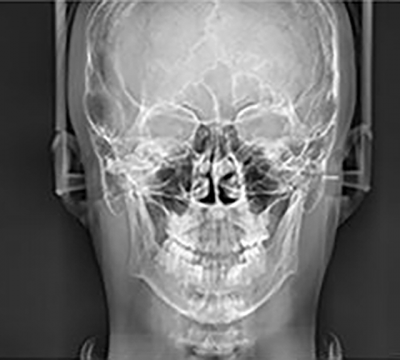

CEPHALOMETRIC (SCAN CEPH)

The PaX-i provides optimal images exclusively designed for orthodontics.

There are two image sizes available, Lateral and Full Lateral, allowing you to choose your image size based on your diagnostic needs.

CEPHALOMETRIC (SCAN CEPH)

The PaX-i provides optimal images exclusively designed for orthodontics.

There are two image sizes available, Lateral and Full Lateral, allowing you to choose your image size based on your diagnostic needs.

LATERAL

Provides specialized high quality images to suit orthodontics and maxillofacial surgeries

LATERAL

Provides specialized high quality images to suit orthodontics and maxillofacial surgeries